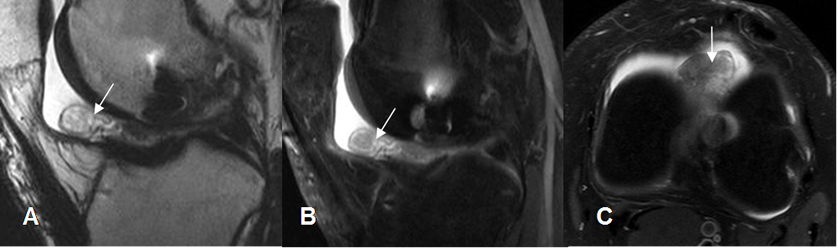

Fig 139. Ruptura parcial del injerto.

A: RM sagital en T2 y B: RM sagital en STIR. Injerto adelgazado, por ruptura parcial.

Fig 140. Ruptura del injerto.

A: RM sagital en T1. No se identifican las fibras del injerto y en su topografía existe tejido de granulación.

B: RM sagital en T2 y C: RM sagital en STIR. Ruptura casi completa del injerto, el cual está rodeado por tejido fibroso.

Fig 141. Ruptura del injerto.

A: RM sagital en T1 y B: RM sagital en STIR. Solución de continuidad del injerto, por ruptura completa.

Fig 142. Ruptura del injerto.

A: RM sagital en T2. Pérdida de la tensión y orientación en las fibras del injerto, sospechando su ruptura.

B: ArtroRM sagital en STIR. Se confirma la ruptura de injerto, con interrupción de sus fibras.